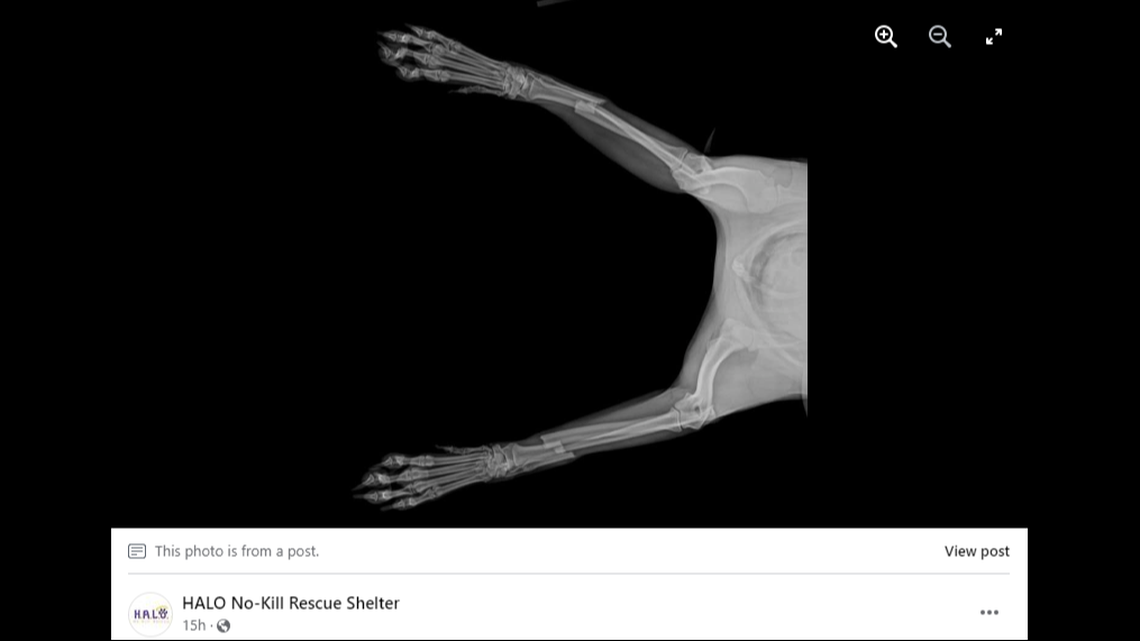

Cody, a 10-month-old miniature Australian shepherd, broke both his front legs when he jumped from the top of a bunk bed, the rescue said.

The force of his landing on the ground broke both of his front legs, the rescue said, an incredibly serious injury. His owners brought him to an Indian River County veterinary office to see what could be done.

In order to fix his legs, Cody needed a surgery that could cost more than $10,000, the rescue said.

“It is typically $5,000 per leg to do it right,” Petrone said. “That is plates with plasma protein and bone marrow transplants. This gives Cody (an) 80% higher chance at a full recovery.”